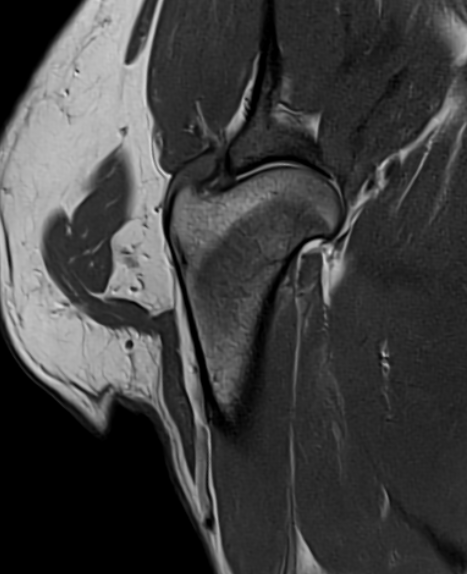

MRI

We have recently undergone software upgrades to our 1.5T MRI facility resulting in even greater image detail and reduced scan times, allowing reduced anaesthesia times for our patients. The quality of images of structures such as the brain, eye, spinal cord, and musculoskeletal system is exceptional.

We accept appropriate outpatient referrals for stable patients and perform a wide range of studies for our medicine and surgery service inpatients. For more information about our MRI service, you can call or email the Radiology department and speak with our MIT, charge nurse or radiologists.